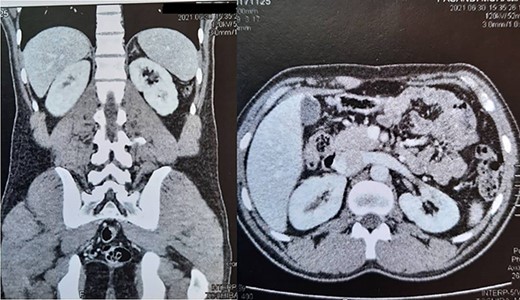

A 22-year-old man was referred to our clinic with ambiguous abdominal pain radiating to the left flank. The patient had a history of diabetes mellitus from 3 years ago. Also, he had a familial history of renal failure due to bilateral renal mass resection in his father. The physical examination revealed a left flank mass. The laboratory tests, including renal function and liver tests, were routine except for microscopic hematuria. In contrast-enhanced abdominal computed tomography scan, huge left renal mass with contrast enhancement was a noticeable finding (Fig. 1). The patient was scheduled for radical nephrectomy, but due to the family’s history of bilateral renal tumor and concern of patients regarding contralateral tumors in the future, he refused to undergo radical nephrectomy. Due to the size of the tumor, we choose to perform open surgery. The operation was performed through a flank incision in the bed of the 12th rib. Despite the large tumor size, we approached the tumor extraperitoneal. During the surgery, we encountered a vast left renal mass. Initially, we released the ureter to avoid accidental injury, then obtained early access to the renal pedicle to control bleeding with a Satinsky clamp.